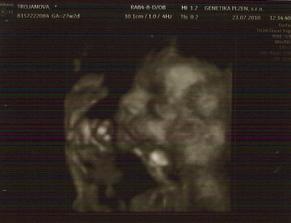

23.7.2010 jdeme na 3D ultrazvuk 🙂 - 27tt+2

3D ultrazvuk byl prostě bomba, všechno nám pan doktor zkontroloval

takže máme 34cm a 1,4kg a máme všechno co máme mít

pohlaví jsme si říct nakonec nenechali, tak se necháme překvapit a v říjnu uvidíme 🙂